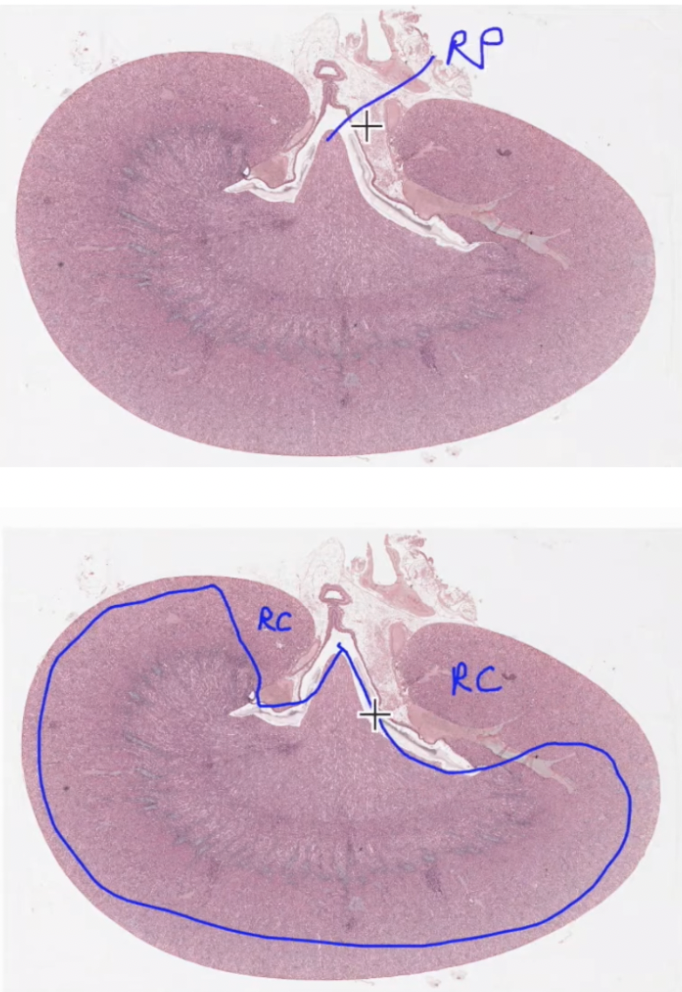

Kidney

Outer cortex

And inner medullary region

Renal pyramid, point/peak at renal papillae where urine drips out

kidney:

Cortical tissue

Proximal distal convoluted tubules

Medullary rays and renal corpuscles

Outer renal cortex contains:

Renal corpuscle (macula densa)

Distal and proximal convoluted tubules

Medullary rays

Stripes are medullary rays (extensions of medullary projecting towards edge)

Collecting ducts and loop of henle

In between are cortical tissue

kidney;

Renal corpuscles are the onion shapes

Tubules surround it

Distal convoluted tubules clearer lumen (cuboidal)

Proximal convoluted tubules have brush border (cuboidal epi)

Distal convuluted vs proximal convuluted tubules in kidney

thin ascending to thick ascending

thick descending to thin descending

Thin segments have either low cuboidal or simple squamous epithelium (look similar to capillaries or small veins)

Thick ascending limb and distal convoluted tubules are lined with cuboidal epithelium without a brush border

kdieny renal corpuscle

Outer parietal layer of bowmans capsule of ss